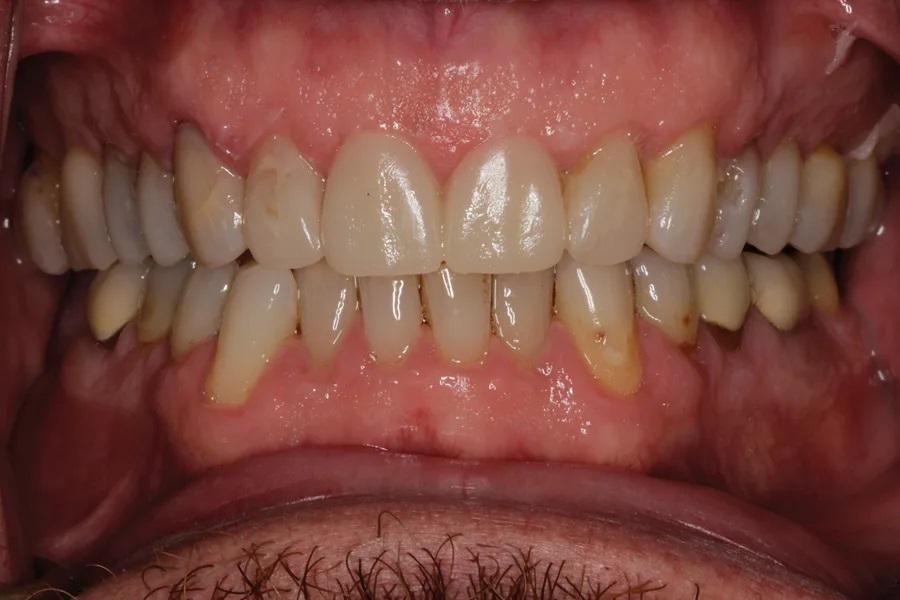

Мужчина, 45 лет. Основная жалоба — неловкость при улыбке из-за коротких, деформированных и измененных в цвете зубов. Обследование выявило гингивит с соответствующей потерей прикрепления, множественные кариозные поражения, износ зубов и реставраций (Фото 1 – Фото 3). Зафиксирован ограниченный паттерн жевания (ОПЖ), что определило умеренный функциональный риск и необходимость учета окклюзии в плане лечения.

Фото 3. Вид с ретракторами до лечения. Износ, истончение эмали, окрашивание зубов.